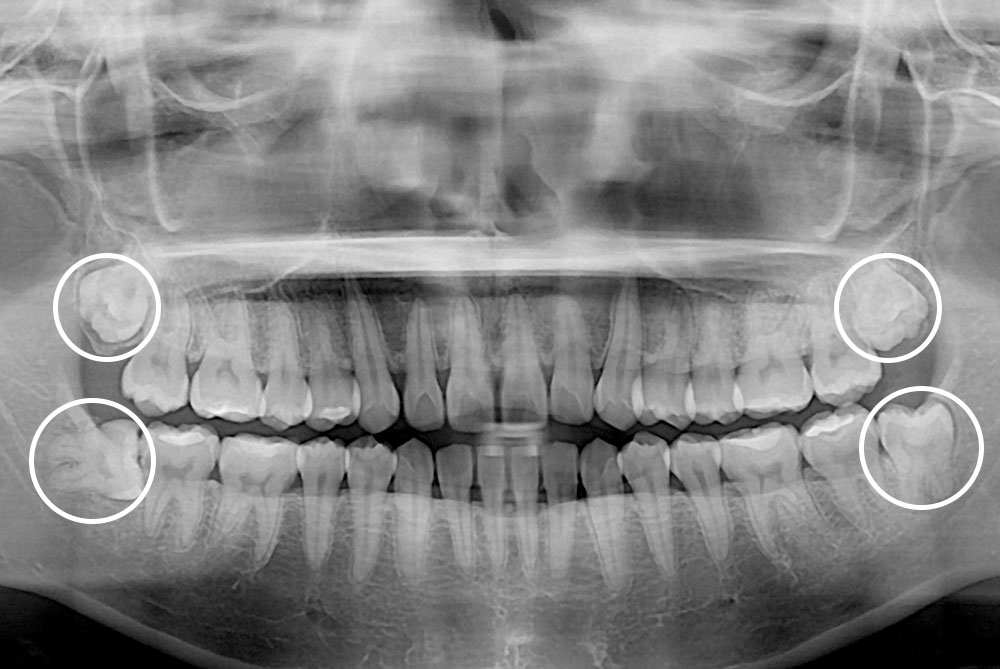

[사랑니] 매복 사랑니 발치

치료후 : 2019-04-11

세종치과는 구강악안면외과학 박사이신 원장님이 발치하는 치과입니다.